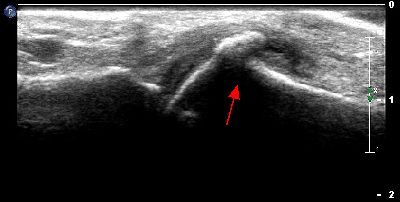

Microavulsione falange distale primo dito (img. 02) microavulsione falange distale primo dito 02